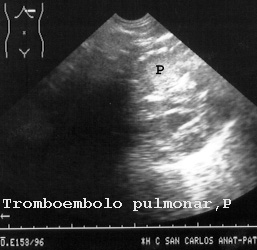

En este otro caso la arteria pulmonar está obstruida por un tromboémbolo que demostramos al punzarlo (Figs 26).

26TEP.JPG (24024 bytes)

Fig 26